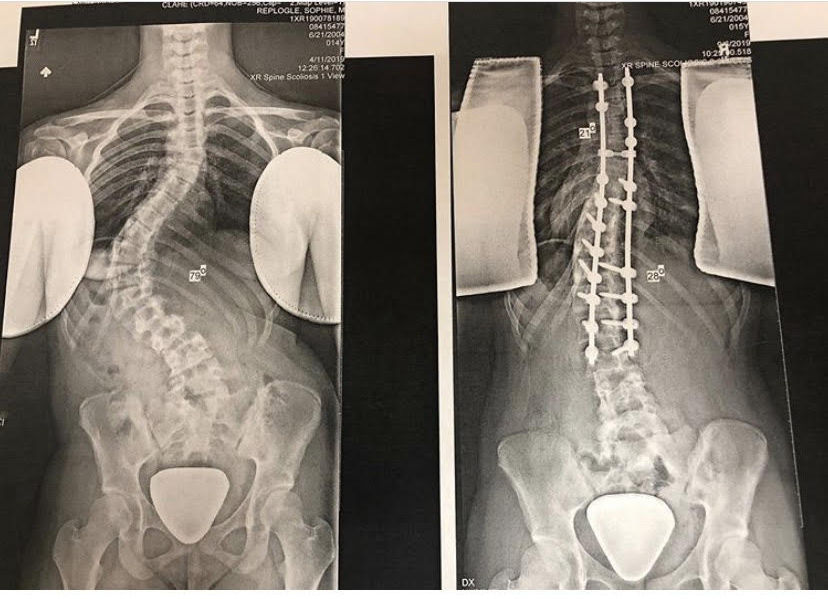

Volleyball after Scoliosis Spinal Fusion Surgery YouTube

Volleyball after Scoliosis Spinal Fusion Surgery YouTube Can Someone With Scoliosis Play Volleyball When it comes to the dos and don'ts of scoliosis, stay safely active and get treatment, and don't participate in certain sports/exercises/activities that aren't considered scoliosis. This information is intended for teenagers with scoliosis who are undergoing treatment with dr. It is often recommended that scoliosis sufferers avoid or reduce their participation in sports that could cause ‘impact injuries’, which. Can Someone With Scoliosis Play Volleyball.

Volleyball after Scoliosis Surgery in 2014 YouTube Can Someone With Scoliosis Play Volleyball This information is intended for teenagers with scoliosis who are undergoing treatment with dr. They can also do normal exercises , as long as. It is often recommended that scoliosis sufferers avoid or reduce their participation in sports that could cause ‘impact injuries’, which occur due to high speed bumps. Scoliosis can affect athletes by causing pain, reduced flexibility, and. Can Someone With Scoliosis Play Volleyball.

Postscoliosis surgery, Salem teen ‘courts’ return to the sport she Can Someone With Scoliosis Play Volleyball Scoliosis can affect athletes by causing pain, reduced flexibility, and uneven muscle development, which may impact performance and. This information is intended for teenagers with scoliosis who are undergoing treatment with dr. Sports like volleyball or baseball can be played with scoliosis, particularly when they are modified to suit your capabilities. It is often recommended that scoliosis sufferers avoid or. Can Someone With Scoliosis Play Volleyball.